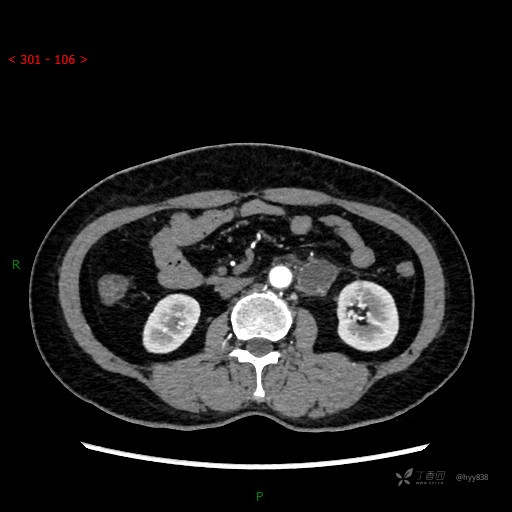

增强动脉期

静脉期

CT平扫是外院的,因图像质量原因,不方便上传!